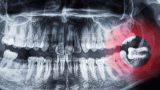

虫歯は初期の段階ではほとんど痛みはなく、虫歯が大きくなると痛みが出ますが、神経のない歯は虫歯になっても痛むことがなく進行してしまい、被せ物の中で虫歯がどんどん広がっていることもあります。

歯周病は痛みがほとんどないまま進行してしまい、症状が出た時にはかなり進行してしまっていることが多く、歯を失う原因の1位です。

病気に気づかずにいると、最悪歯を抜かないといけなくなります。